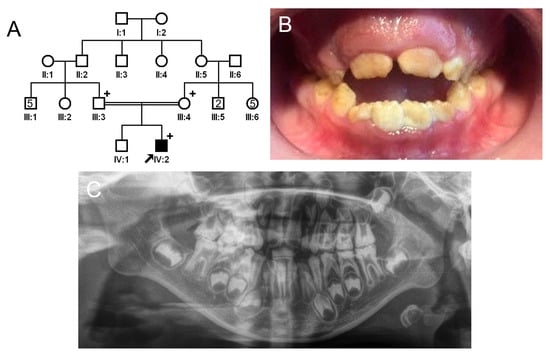

The proband of family 2 was a 7-year-old male, the second child from a consanguineous Turkish family (Figure 3). He had no other remarkable past medical history. His newly erupted permanent anterior teeth exhibited brown discoloration but a normal shape because the hypomineralized enamel had not yet fractured. However, the remaining deciduous teeth and first permanent molars exhibited apparent attrition and enamel fractures. There were no other affected family members except for the proband; therefore, a recessive or de novo mutation was suspected.

Figure 3.

Pedigree, clinical photo, and panoramic radiograph of family 2. (A) Pedigree of family 2. The black symbol indicates the affected individual, and the proband is indicated by a black arrow. A plus sign above the symbol indicates participating individuals. (B) Clinical photo of the proband at age 7 years. He has an anterior open bite with a constricted maxilla. (C) Panoramic radiograph of the proband at age 7 shows enamel fractures and attrition in almost all posterior teeth including first molars. The affected enamel has reduced radiopacity, making it similar to the underlying dentin.